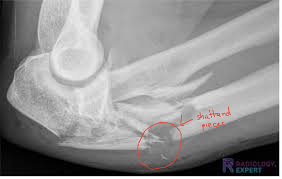

Comminuted

shattered pieces of bone

broken into 3 or more pieces

caused by high impact forces (i.e: car accidents)